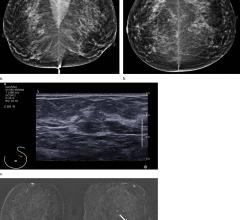

Magnetic resonance imaging (MRI) can be used for breast imaging as an alternative to mammography.

May 9, 2019 — When appropriate, short-interval follow-up magnetic resonance imaging (MRI) can be used to identify early ...

June 22, 2017 — A new article published by JAMA Oncology compares outcomes for combined mammography and magnetic ...

February 21, 2017 — Magnetic resonance imaging (MRI) screening improves early diagnosis of breast cancer in all women ...

February 10, 2017 — A new method for screening women with dense breast tissue may potentially save thousands of lives by ...

February 7, 2017 — A newly developed breast magnetic resonance imaging (MRI) exam protocol, the first of its kind being ...